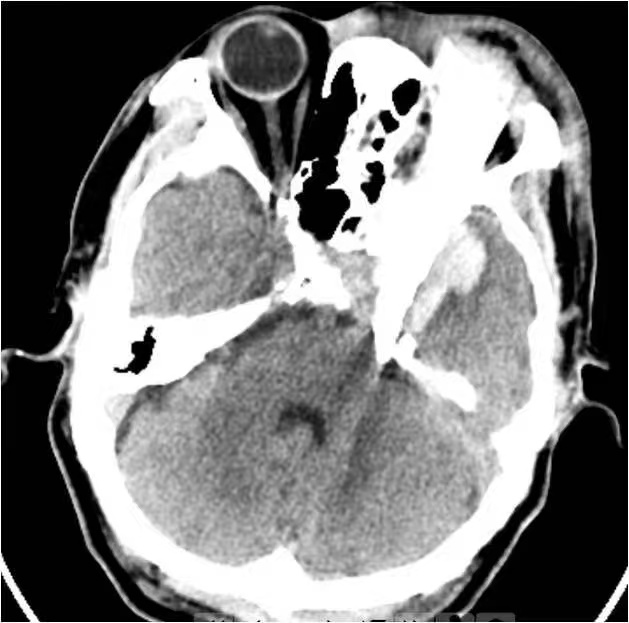

急诊医生首先接诊,在完成新冠病毒肺炎风险排查后,马上为患者安排了颅脑CT检查并请神经外科代从新医生紧急会诊。通过CT影像可见,一块长度超过10cm的玻璃碎片如利刃般自左侧眉弓处刺入眼眶,异物刺破眼眶进入颅内,尖端直抵脑干前方,左侧眼球破裂。更为棘手的是,异物因刺到颅底骨质,颅内玻璃碎为数块,并伴有颞叶脑内血肿形成。万幸的是就诊时患者神志尚清楚。

急诊CT检查结果